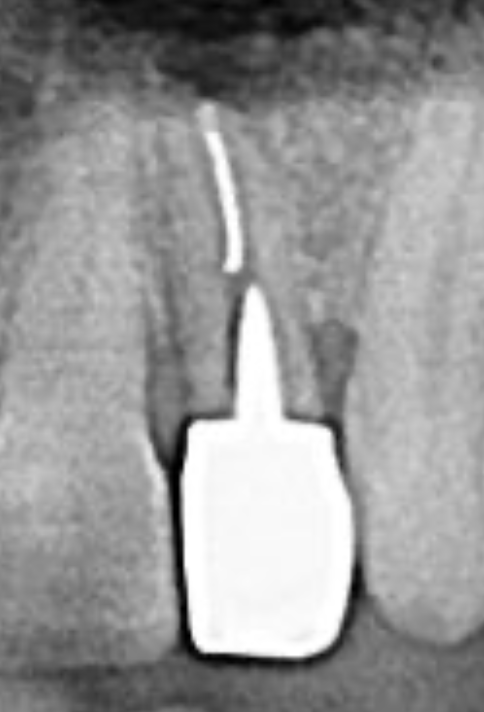

Central Incisor Extraction, Immediate Implant Placement and Provisional Crown Delivery with Guided Tissue Regeneration

0 0 0